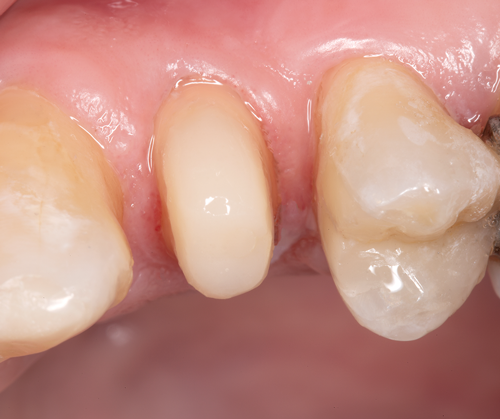

Fig 3. After endodontic treatment, crown lengthening was performed to develop an ideal ferrule effect.

Figure 3

Fig 4. An adequate collar effect of 2 mm of sound tooth structure would provide an anti-rotational feature for the stability of the crown.

Figure 4

Fig 5. Buccal view of optimal ferrule effect with a healthy biological framework.

Figure 5